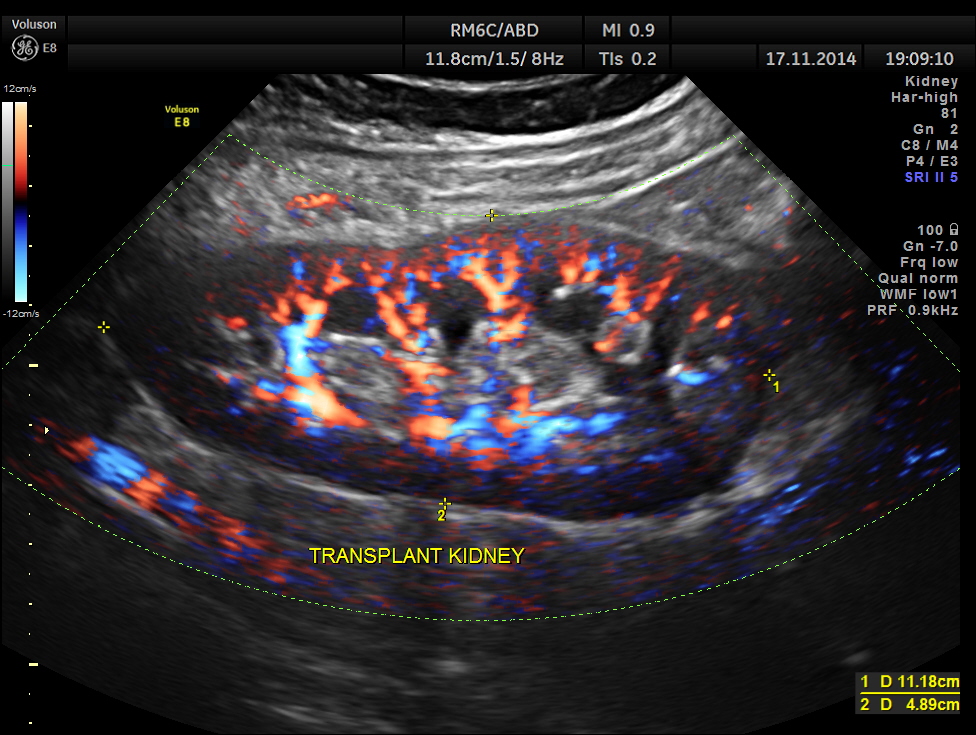

The following pictures show the transplanted kidney in the Right Iliac Fossa, with normal architecture, good Power Doppler flow and normal Spectral Doppler values.